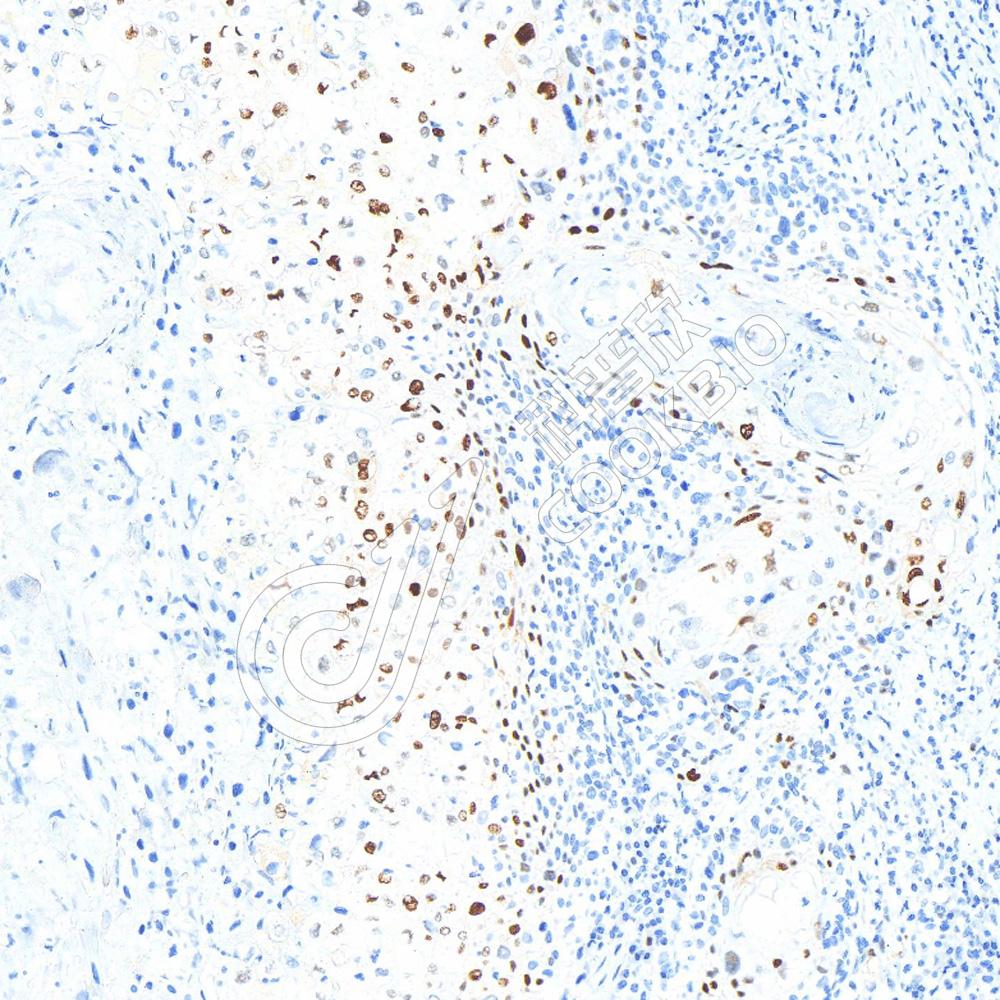

IHC检测p21蛋白(货号 K5450114).

样品: 人皮肤鳞状细胞癌, 4%多聚甲醛 (货号KSG1101) 固定12-24小时.

抗原修复: 柠檬酸抗原修复液(干粉, pH 6.0) (KSG1201), 高压锅均匀喷气计时2分钟.

—抗: 1: 700稀释, 4℃ 孵育过夜.

二抗: S-vision免疫组化多聚二抗(山羊抗兔),即用型 (货号KB3906), 室温孵育20分钟.